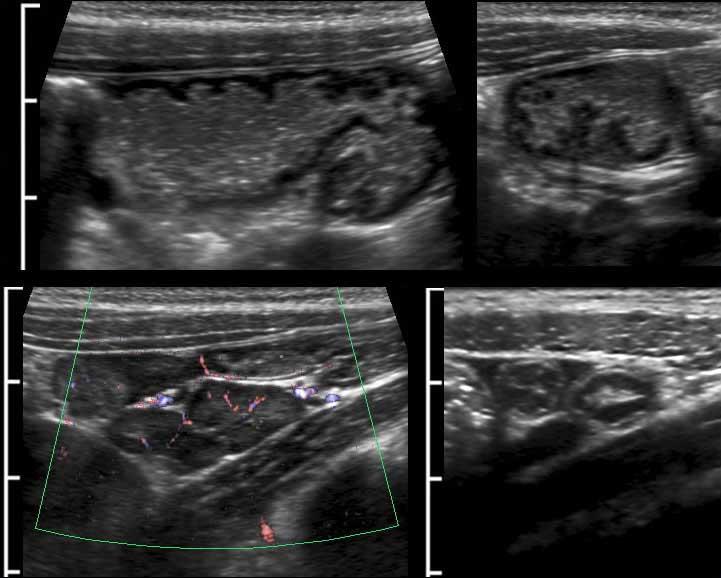

Sigmoid diverticulosis in four different patients.

Các túi thừa chứa đầy phân được quan sát rõ nhất khi đại tràng co lại.

Chúng biểu hiện là các cấu trúc phản âm sáng với bóng cản âm ở bờ ngoài của đại tràng.

Lưu ý độ dày thay đổi của lớp cơ ở bốn bệnh nhân này.

Hình ảnh siêu âm chi tiết của túi thừa đại tràng sigma ở bệnh nhân 61 tuổi rất gầy.

Có một ít phân trong lòng đại tràng sigma và một sỏi phân lớn trong túi thừa (mũi tên).

Lưu ý thành túi thừa rất mỏng, bao gồm lớp (dưới)niêm mạc thoát vị được bao phủ bởi một lớp thanh mạc rất mỏng.

Sự thoát vị qua lớp cơ, luôn luôn xảy ra tại điểm yếu nơi các mạch máu xuyên qua lớp cơ vòng, ngay cạnh dải cơ dọc kết tràng (mũi tên). Các mạch máu xuyên này được xác định bằng Doppler màu ở một bệnh nhân rất gầy khác (dưới bên trái) và được minh họa trong hình ảnh Netter ở dưới bên phải.